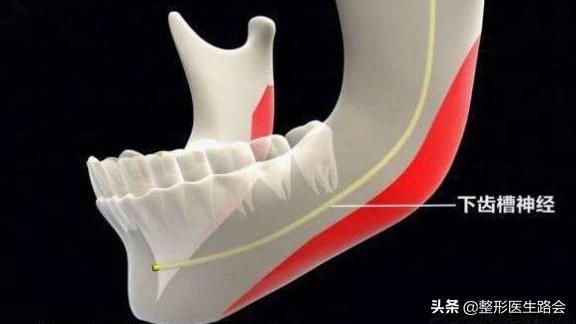

截多截少是根据术前的周密检查、如何在不伤神经的前提下进行,有些求美者检查片子一出来,神经线非常低,那么截取骨量必然会少。

而对于越俎代庖要求医生多去点骨头的求美者,我一般都是拒绝的,安全原则是一切总则。

下颌角神经线